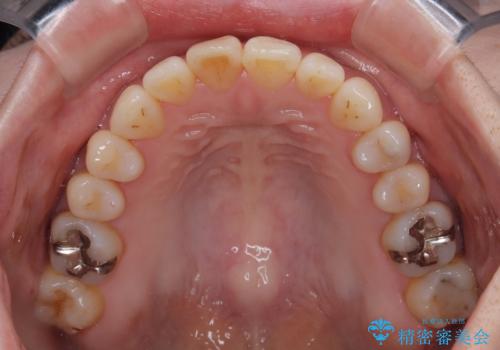

前歯のデコボコをインビザライン・モデレートで矯正治療

- 上下前歯のデコボコを気にして来院された患者様です。

安価なインビザラインパッケージを用いての治療を希望されており、デコボコの程度が中等度であったため、インビザライン・モデレートを用いて矯正治療を行うこととしました。